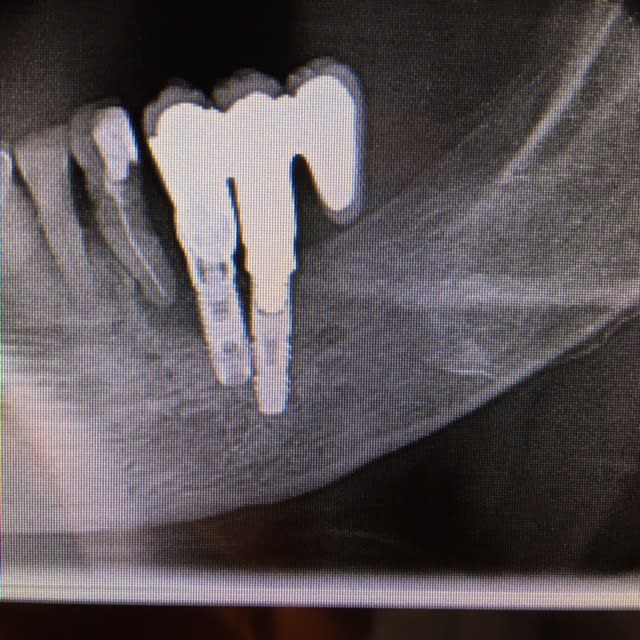

des deux implants posés (jetés ) par un confrère,

35 est un FRIALIT 2

qq'un peut me dire marque et modèle de 34 ?

dommage que la radio soit pas bien centrée sur l'implant recherché...mais il a une bonne tête de screwvent zimmer...